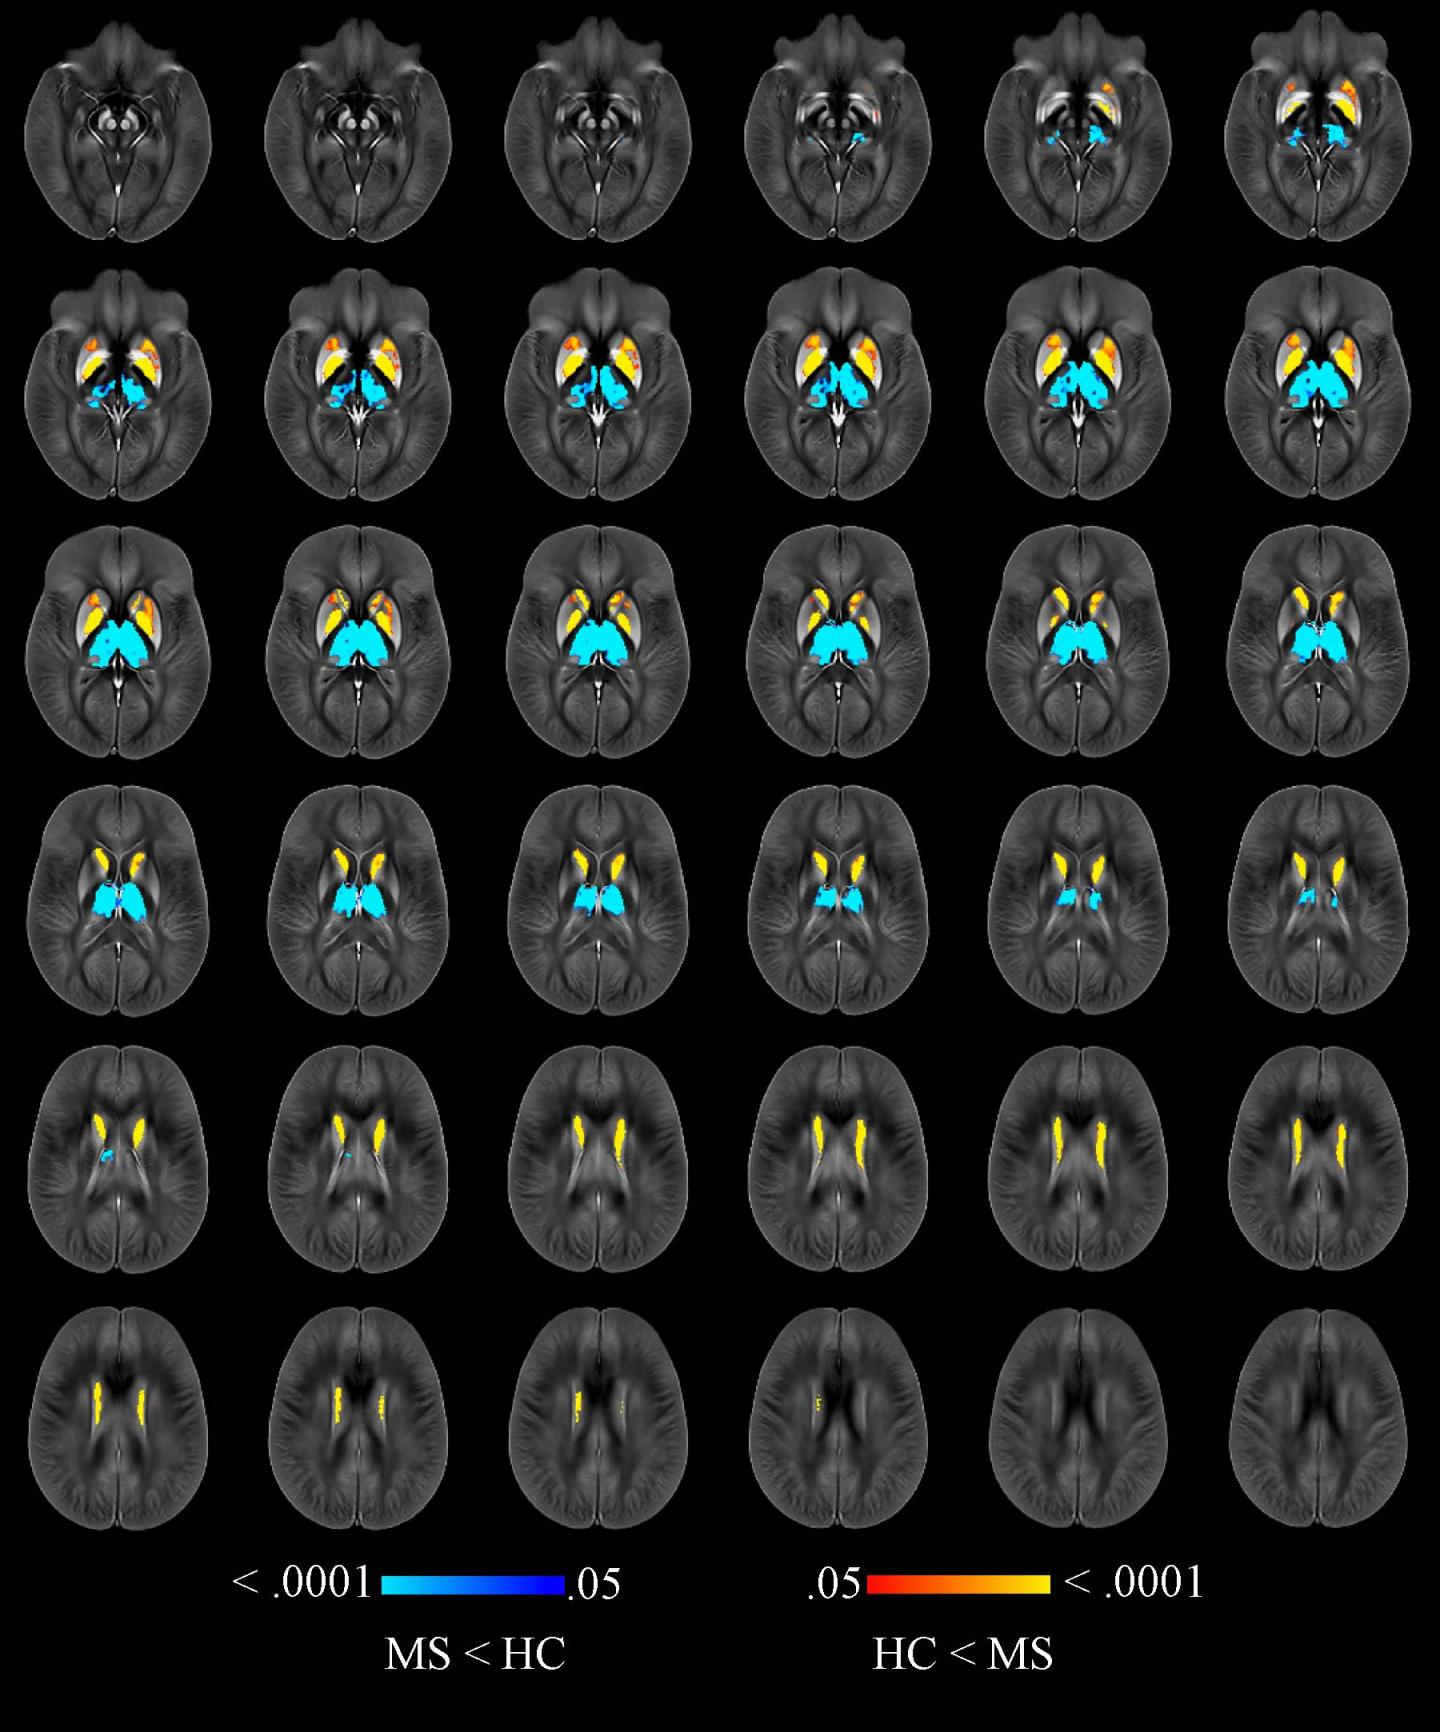

Dr. Zivadinov and colleagues recently compared brain iron levels in people with MS to those of a healthy control group using an advanced MRI technique called quantitative susceptibility mapping. A brain region with more iron would have higher magnetic susceptibility, and one with less iron would have lower susceptibility.

The researchers performed the mapping technique on 600 MS patients, including 452 with early-stage disease and 148 whose disease had progressed.

Compared to 250 healthy control participants, MS patients had higher levels of iron in the basal ganglia, a group of structures deep in the brain that are central to movement. However, the MS patients had lower levels of iron in their thalamus, an important brain region that helps process sensory input by acting as a relay between certain brain structures and the spinal cord. The lower iron content in the thalamus and higher iron content in other deep gray matter structures of people with MS were associated with longer disease duration, higher disability degree and disease progression.

This association with clinical disability persisted even after adjusting for changes in the brain volumes of each individual structure.

"In this large cohort of MS patients and healthy controls, we have reported, for the first time, iron increasing in the basal ganglia but decreasing in thalamic structures," Dr. Zivadinov said. "Iron depletion or increase in several structures of the brain is an independent predictor of disability related to MS."

The results point to a potential role for quantitative susceptibility mapping in clinical trials of promising new drugs, Dr. Zivadinov said. Current treatments involving anti-inflammatory drugs do not prevent MS patients from developing disability.